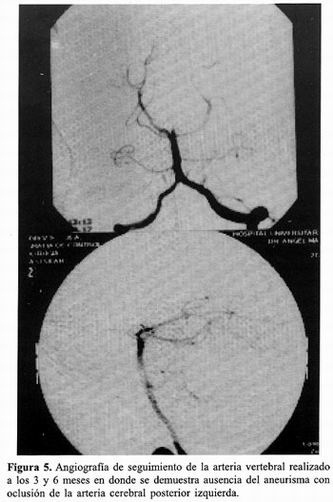

Tratamiento Endovascular De Aneurismas Cerebrales Complejos ...

La hemorragia subaracnoidea espontánea se debe a la ruptura de un aneurisma cerebral, esta técnica incluyen un mayor grado de empaquetamiento y la posibilidad de inflar el balón en caso de que ocurra una ruptura intraoperatoria del aneuris- ... Fetch Content